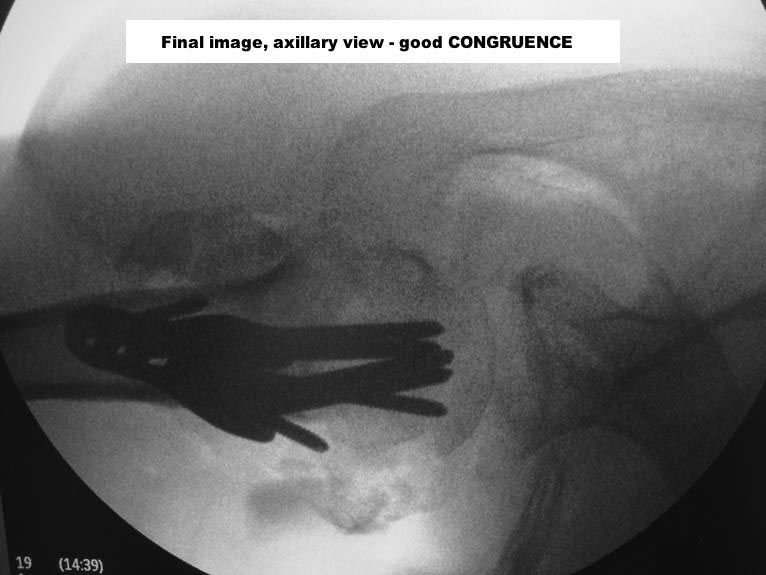

With a good PHILOS, surgeon must re-establish the best cephalic-diaphyseal angle (head-shaft relation) he can, and fix that

GT and LT shall be fixed with bony sutures, in usual fashion

Here are some photos, of chronic, locked, 4 part posterior dislocation, 2 months old, that I did September/2011. Patient is 67, very, very active - had a really reasonable, honest clinical result ...

Photos attached ...